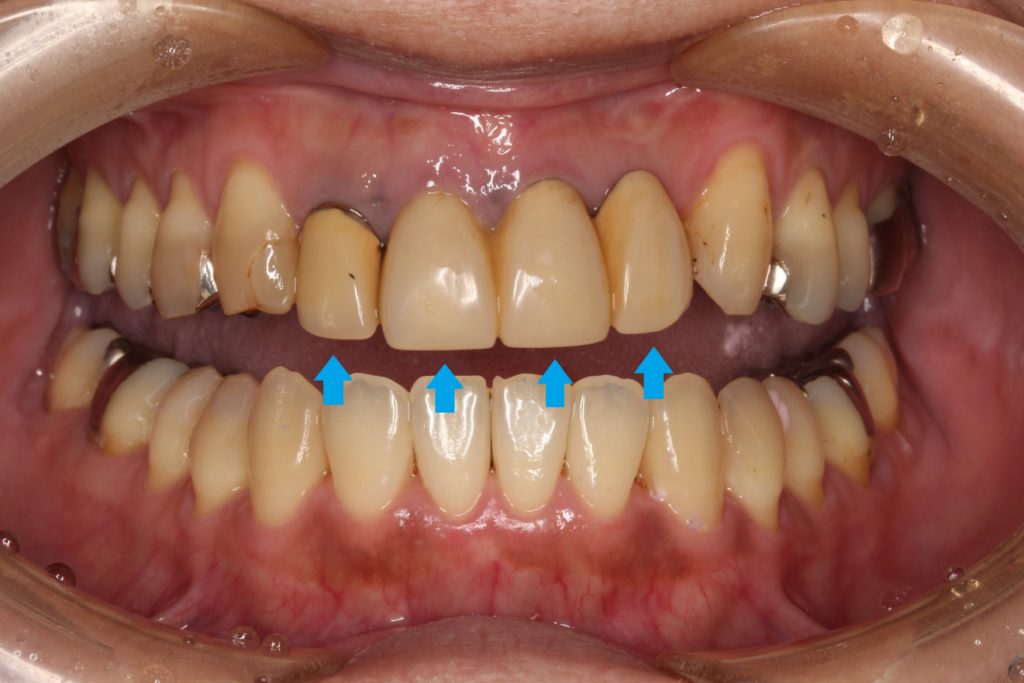

今回は前歯の審美治療の紹介です。

40代女性の患者さんです。

「昔に保険で治したブリッジの差し歯を綺麗にしたい」

と当院を来院されました。

お口の中を見てみると、

このような状態です。

前歯の4本がぶせ物で治療がされています。

こちらの4本ですね。

20年以上まえの治療で、歯が黄色く黄ばんで、歯の根元が黒くなっている箇所もあります。

こちらは「レジン前装冠」というかぶせ物で、表面の見える所はレジンというプラスティック樹脂で、内部から裏側には金属が使われています。

レジンは経年劣化とともに、黄色く変色してくる欠点があります。

そのために、歯が黄色く変色して、他の歯と色の違いが出てきます。

また内部に金属が使われていると説明しましたが、金属が歯の根元で黒く見える場合があります。